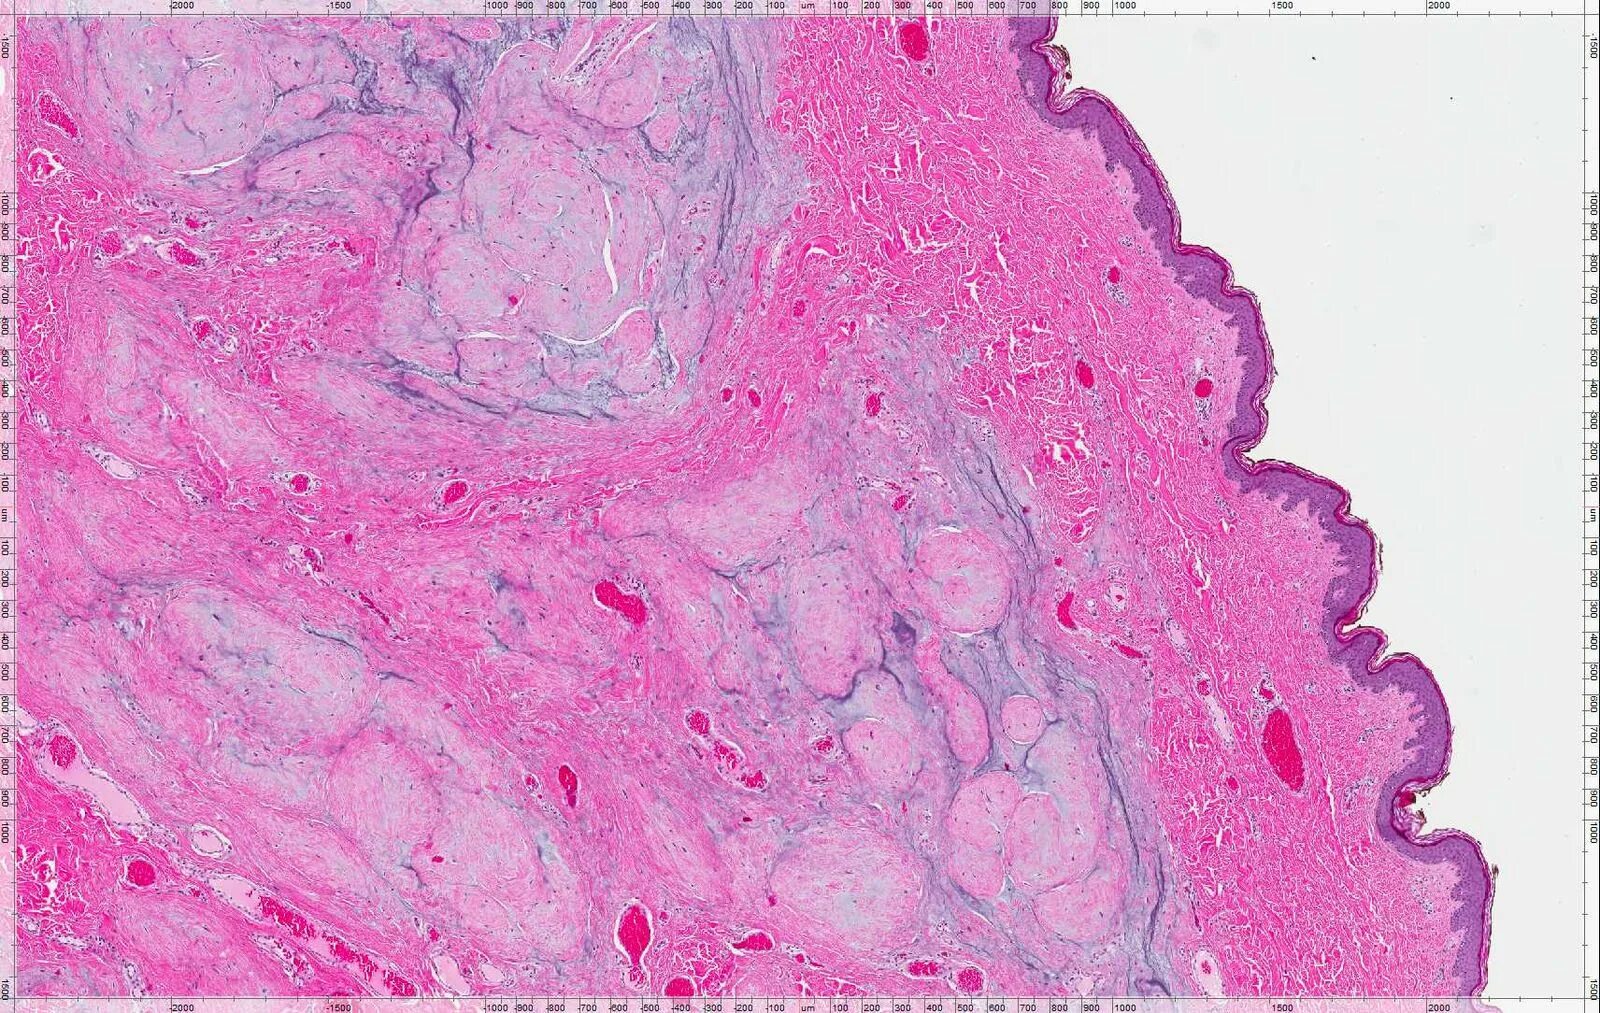

Гистология челюстей